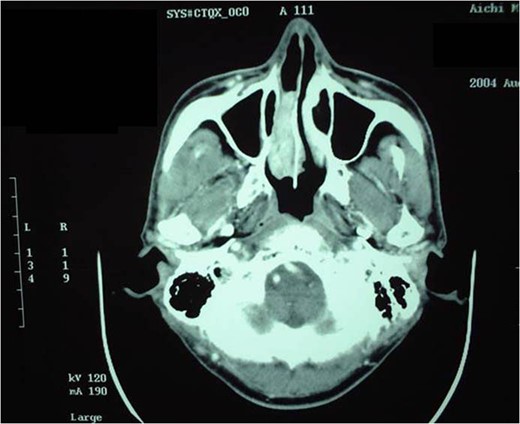

A 57-year-old man with a chief complaint of right nasal obstruction and hemorrhage was referred to our department for detailed examination. His own and family histories were unremarkable. Nasal endoscopy showed a readily bleeding mass between the right nasal septum and inferior turbinate (Fig. 1A). Enhanced CT (Fig. 2) revealed a heterogeneous mass lesion (5 × 1.7 cm) with an enhancement effect that filled the right nasal cavity. The nasal septum and lateral nasal wall were not deformed. Soft-tissue density was observed in the right ethmoid sinus, but was thought to be a mucous thickness due to its difference from the tumor’s density. The tumor evidenced an equivalent signal in the T1 and T2 weighted images of MRI with a strong enhancement effect.

Enhanced CT before rIL-2 administration. A heterogeneous mass lesion with an enhancement effect filled the right nasal cavity.